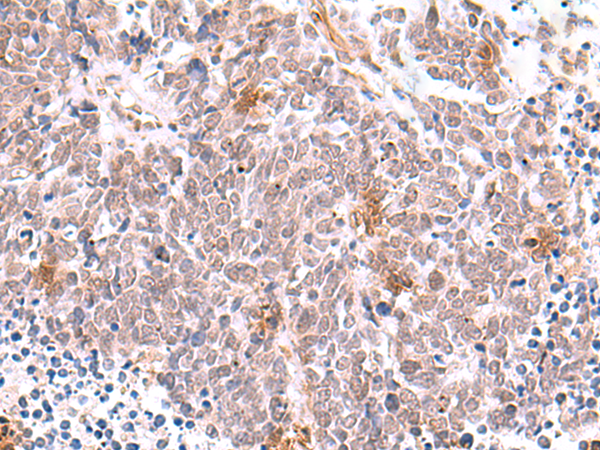

IHC positive control:

Human tonsil and Human lung cancer

IHC Recommend dilution:

50-300